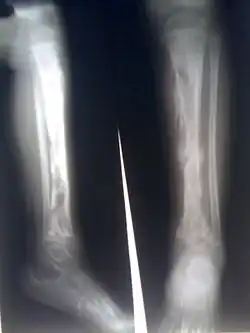

![]() Zánět na holenní kosti, jsou zřetelné četné abscesy | |

Osteomyelitida (osteomyelitis), česky zánět kostní dřeně, je infekční hnisavé onemocnění kostí a kostní dřeně vyvolané bakteriemi či mykobakteriemi. Při tomto onemocnění dochází k ucpávání cév v kosti krevními sraženinami a následnému odumírání kostní tkáně. Může docházet k obrůstání postižených částí okosticí.